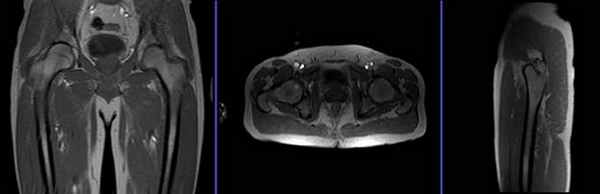

Серия T2 stir, коронарный срез 3 мм до проведения атрографии

Планирование коронарных срезов на аксиальной плоскости; угловое расположение блока должно быть параллельно головкам правой и левой бедренных костей. Проверьте расположение блока на 2-х других плоскостях. Соответствующий угол должен быть получен в сагиттальной плоскости (параллельно бедру). Эти срезы должны полностью покрывать оба тазобедренных сустава, от уровня седалищных бугров до уровня лобкового симфиза.

Серия T1 турбо спин-эхо, аксиальный срез 3 мм, до проведения атрографии

Планирование аксиальных срезов на коронарной плоскости; угловое расположение блока параллельно головкам правой и левой бедренных костей. Проверьте расположение блока на 2-х других плоскостях. Соответствующий угол должен быть получен в сагиттальной плоскости (перпендикулярно бедру). Эти срезы должны полностью покрывать оба тазобедренных сустава, от уровня передневерхней подвздошной ости до малого вертела.